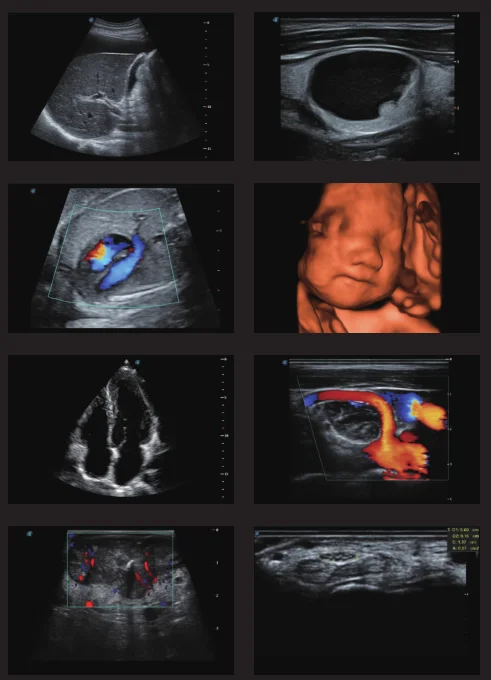

Trolley Color Doppler ultrasound scanner 3D/4D sonoscape P25 machine with a good price.